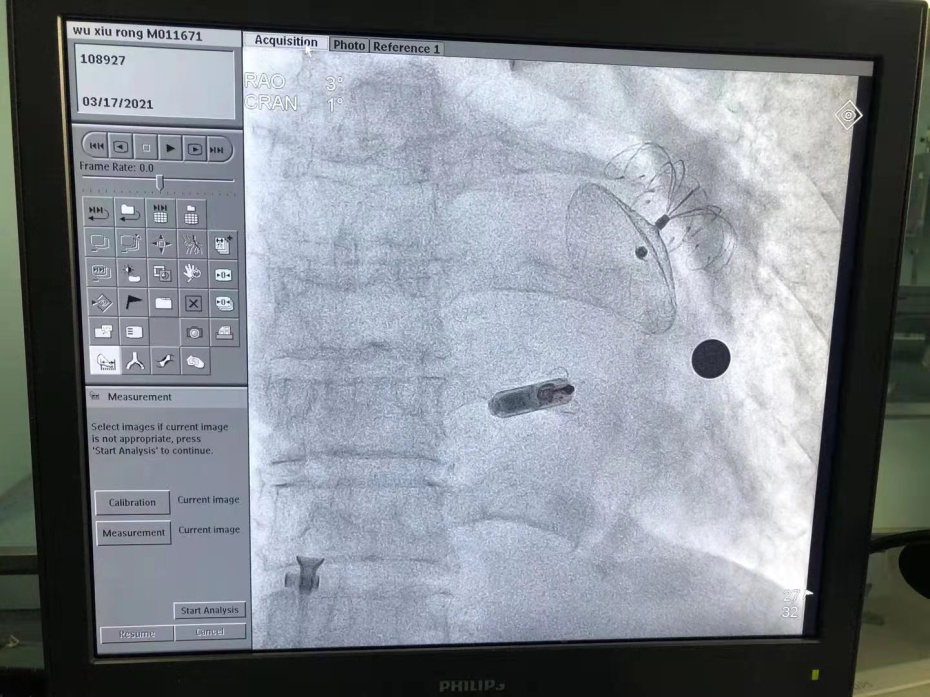

3 月 17 日,杨平珍教授、彭俊主任和心内科介入团队成功将起搏器通过导管植入到患者体内。

手术植入时,「胶囊起搏器」犹如被线牵住的电子小「风筝」,在通过血管送到患者左心室着床后,小「风筝」放飞并独立完成传统起搏器的各项工作。

术中影像